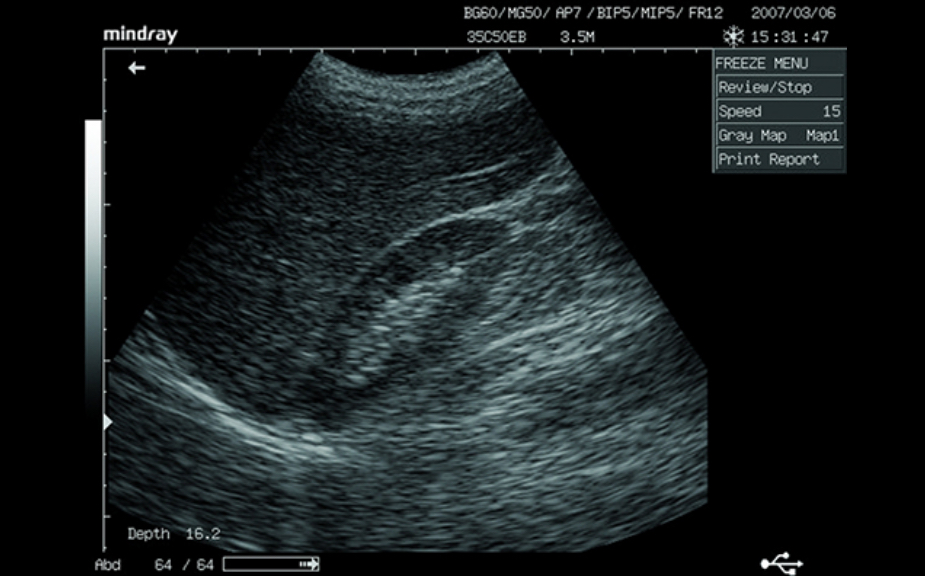

Clinical Images